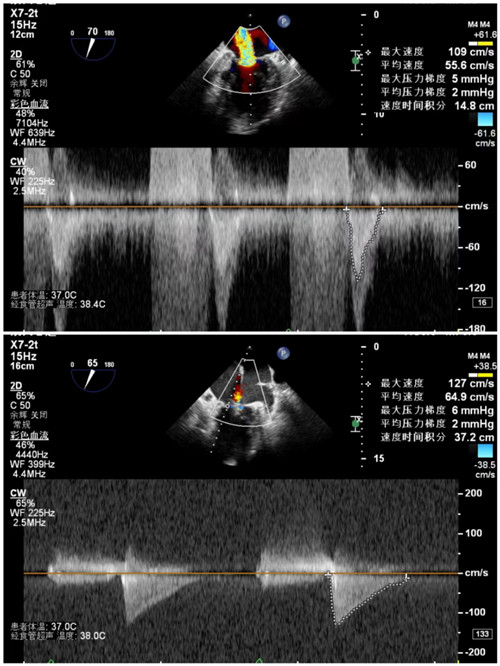

手术前后二尖瓣反流

手术前后二尖瓣压差

7月9日上午,心内科联合麻醉科、胸外科等多学科,共同为陈奶奶开展手术,术前二尖瓣大量反流,反流程度5+,肺静脉反流明显,术后二尖瓣少量反流,反流程度1+,肺静脉反流消失,手术顺利结束。术后安返病房,次日陈奶奶从不能平卧到能下床活动。在医护人员的精心照顾下,陈奶奶现已顺利出院。